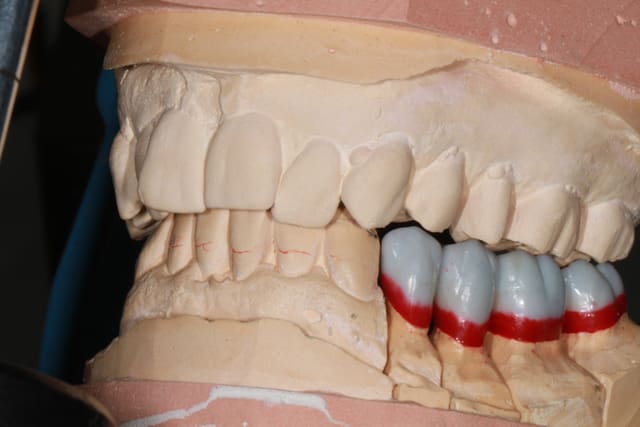

25/09/2013 à 22h10

Wax up et taille crayon...

Empreinte, détourage et préparation des cires avec une occlusion différente de celle du wax up, un peu plus de DV

Le trait rouge sur les incisive donne à peu de chose prêt l'origine...